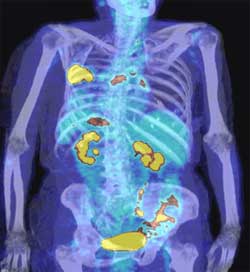

بهبود تصویربرداری «توموگرافی نشر پوزیترون، توموگرافی رایانه‌ای» (PET-CT) با نانوذره‌های برچسب‌دار

محققان بیمارستان عمومی «ماساچوست» و دانشکده ی پزشکی «هاروارد» در تلاش برای کاهش مقدار نانوذره‌های هدفگیر لازم بری تصویربرداری از تومورهای سرطانی، روش ساده‌ای برای تولید نانوذره‌های «اکسید آهن» برچسب‌دار حاوی 18F توسعه داده‌اند.

نتیجه این کار تولید نانوذره‌هایی است که با استفاده از «توموگرافی نشر پوزیترون» (PET)، «توموگرافی رایانه‌ای» (CT) و روش‌های فلورسانس تصویربرداری می‌شوند.

آزمون‌‌های اولیه‌ی نانوذره‌های «اکسید آهن» برچسب‌دار نشان داد که حد تشخیص با استفاده از تصویربرداری «توموگرافی نشر پوزیترون، توموگرافی رایانه‌ای» (PET-CT) حدود 200 برابر کم‌تر از حد قابل‌دسترس توسط تصویربرداری تشدید مغناطیسی است.

تصویربرداری تشدید مغناطیسی روشی استاندارد برای تشخیص نانوذره‌های «اکسید آهن» درون بدن است.

وقتی نانوذره‌های «اکسید آهن» برچسب‌دار به بدن موش تزریق شدند به‌راحتی با استفاده از «توموگرافی نشر پوزیترون، توموگرافی رایانه‌ای» (PET-CT) تشخیص داده شدند.